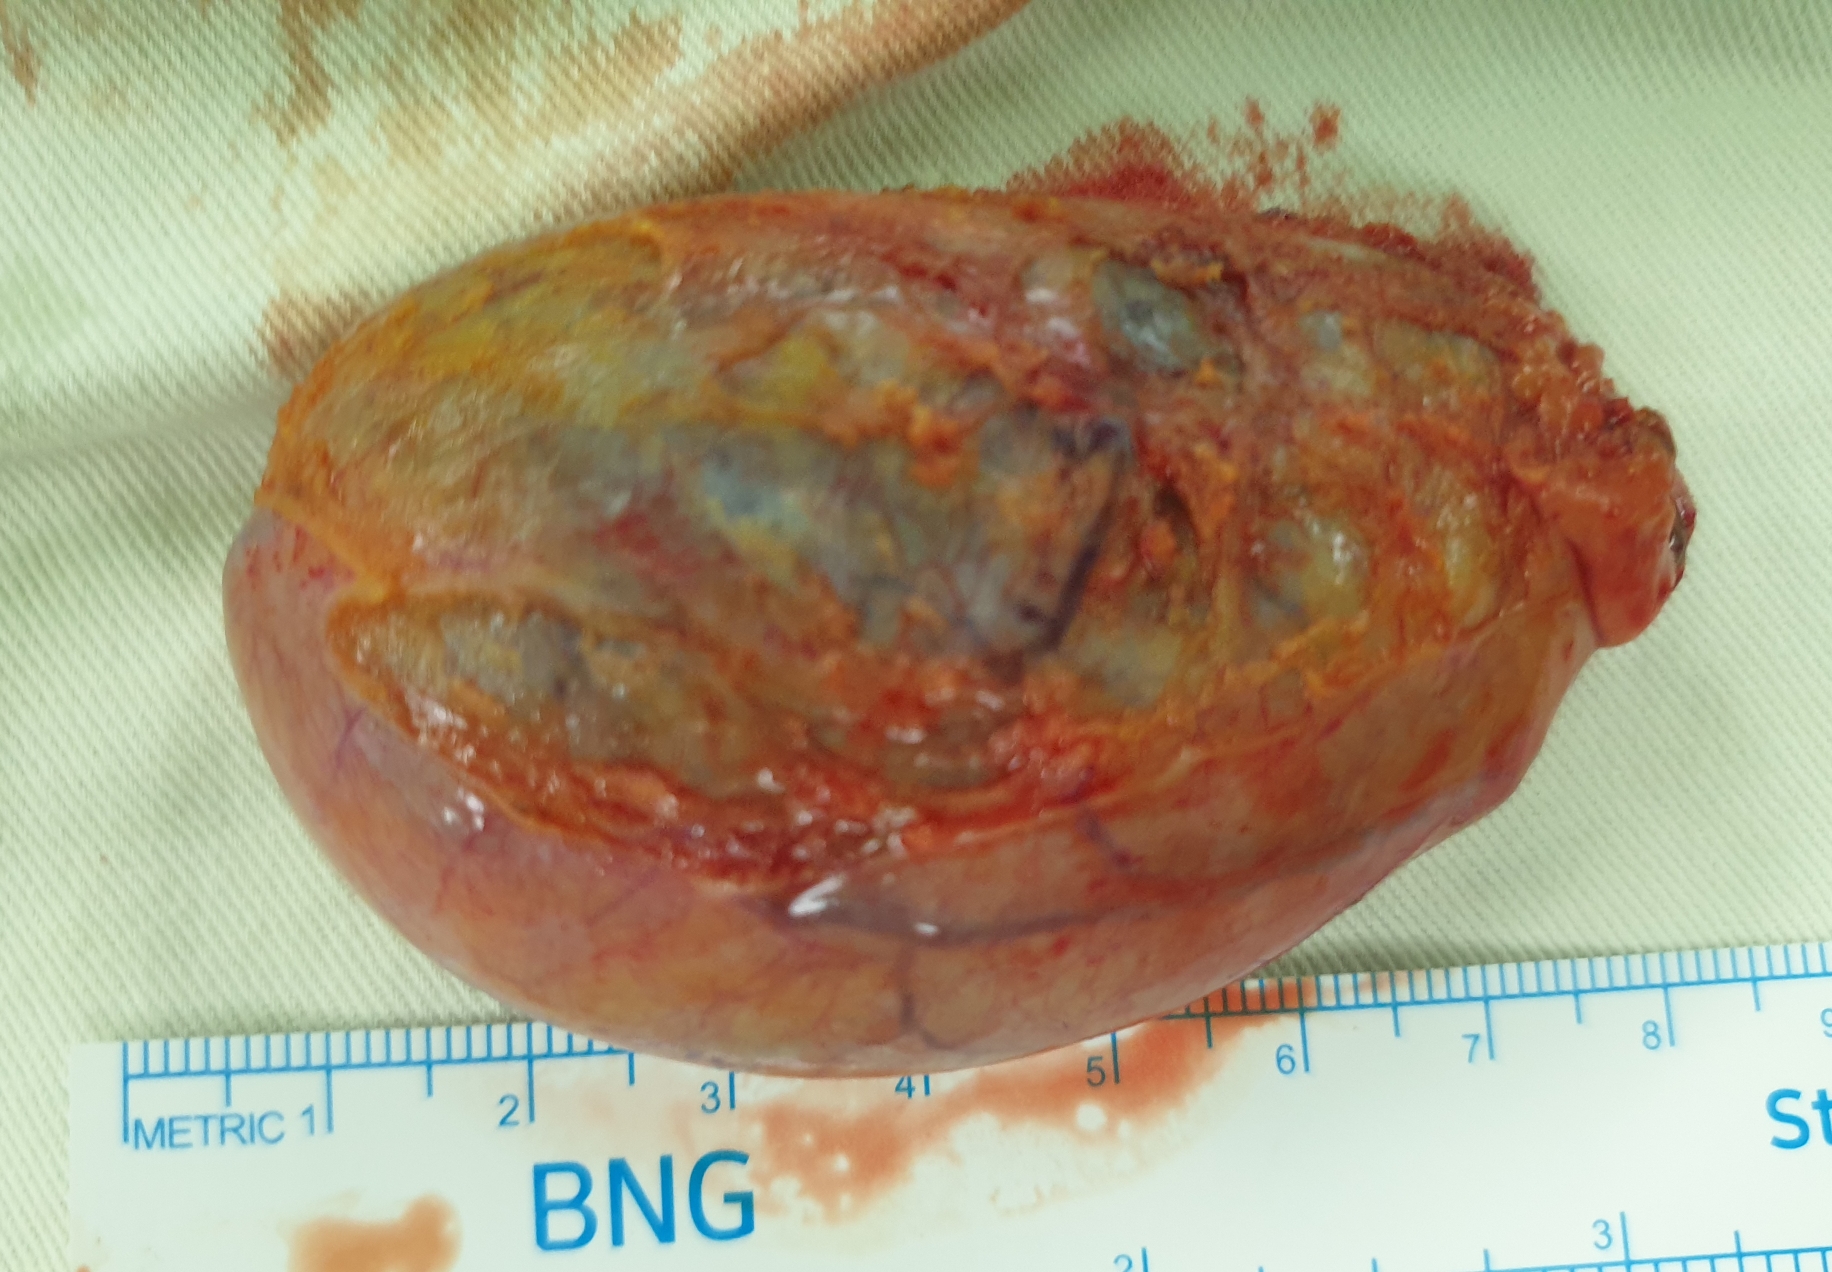

검진으로 동네 내과에서 시행한 복부 초음파상 다발성 담석 소견으로 수술위해 제 외래로 오셨던 분입니다.

방금 복강경 담낭절제술을 시행했습니다.